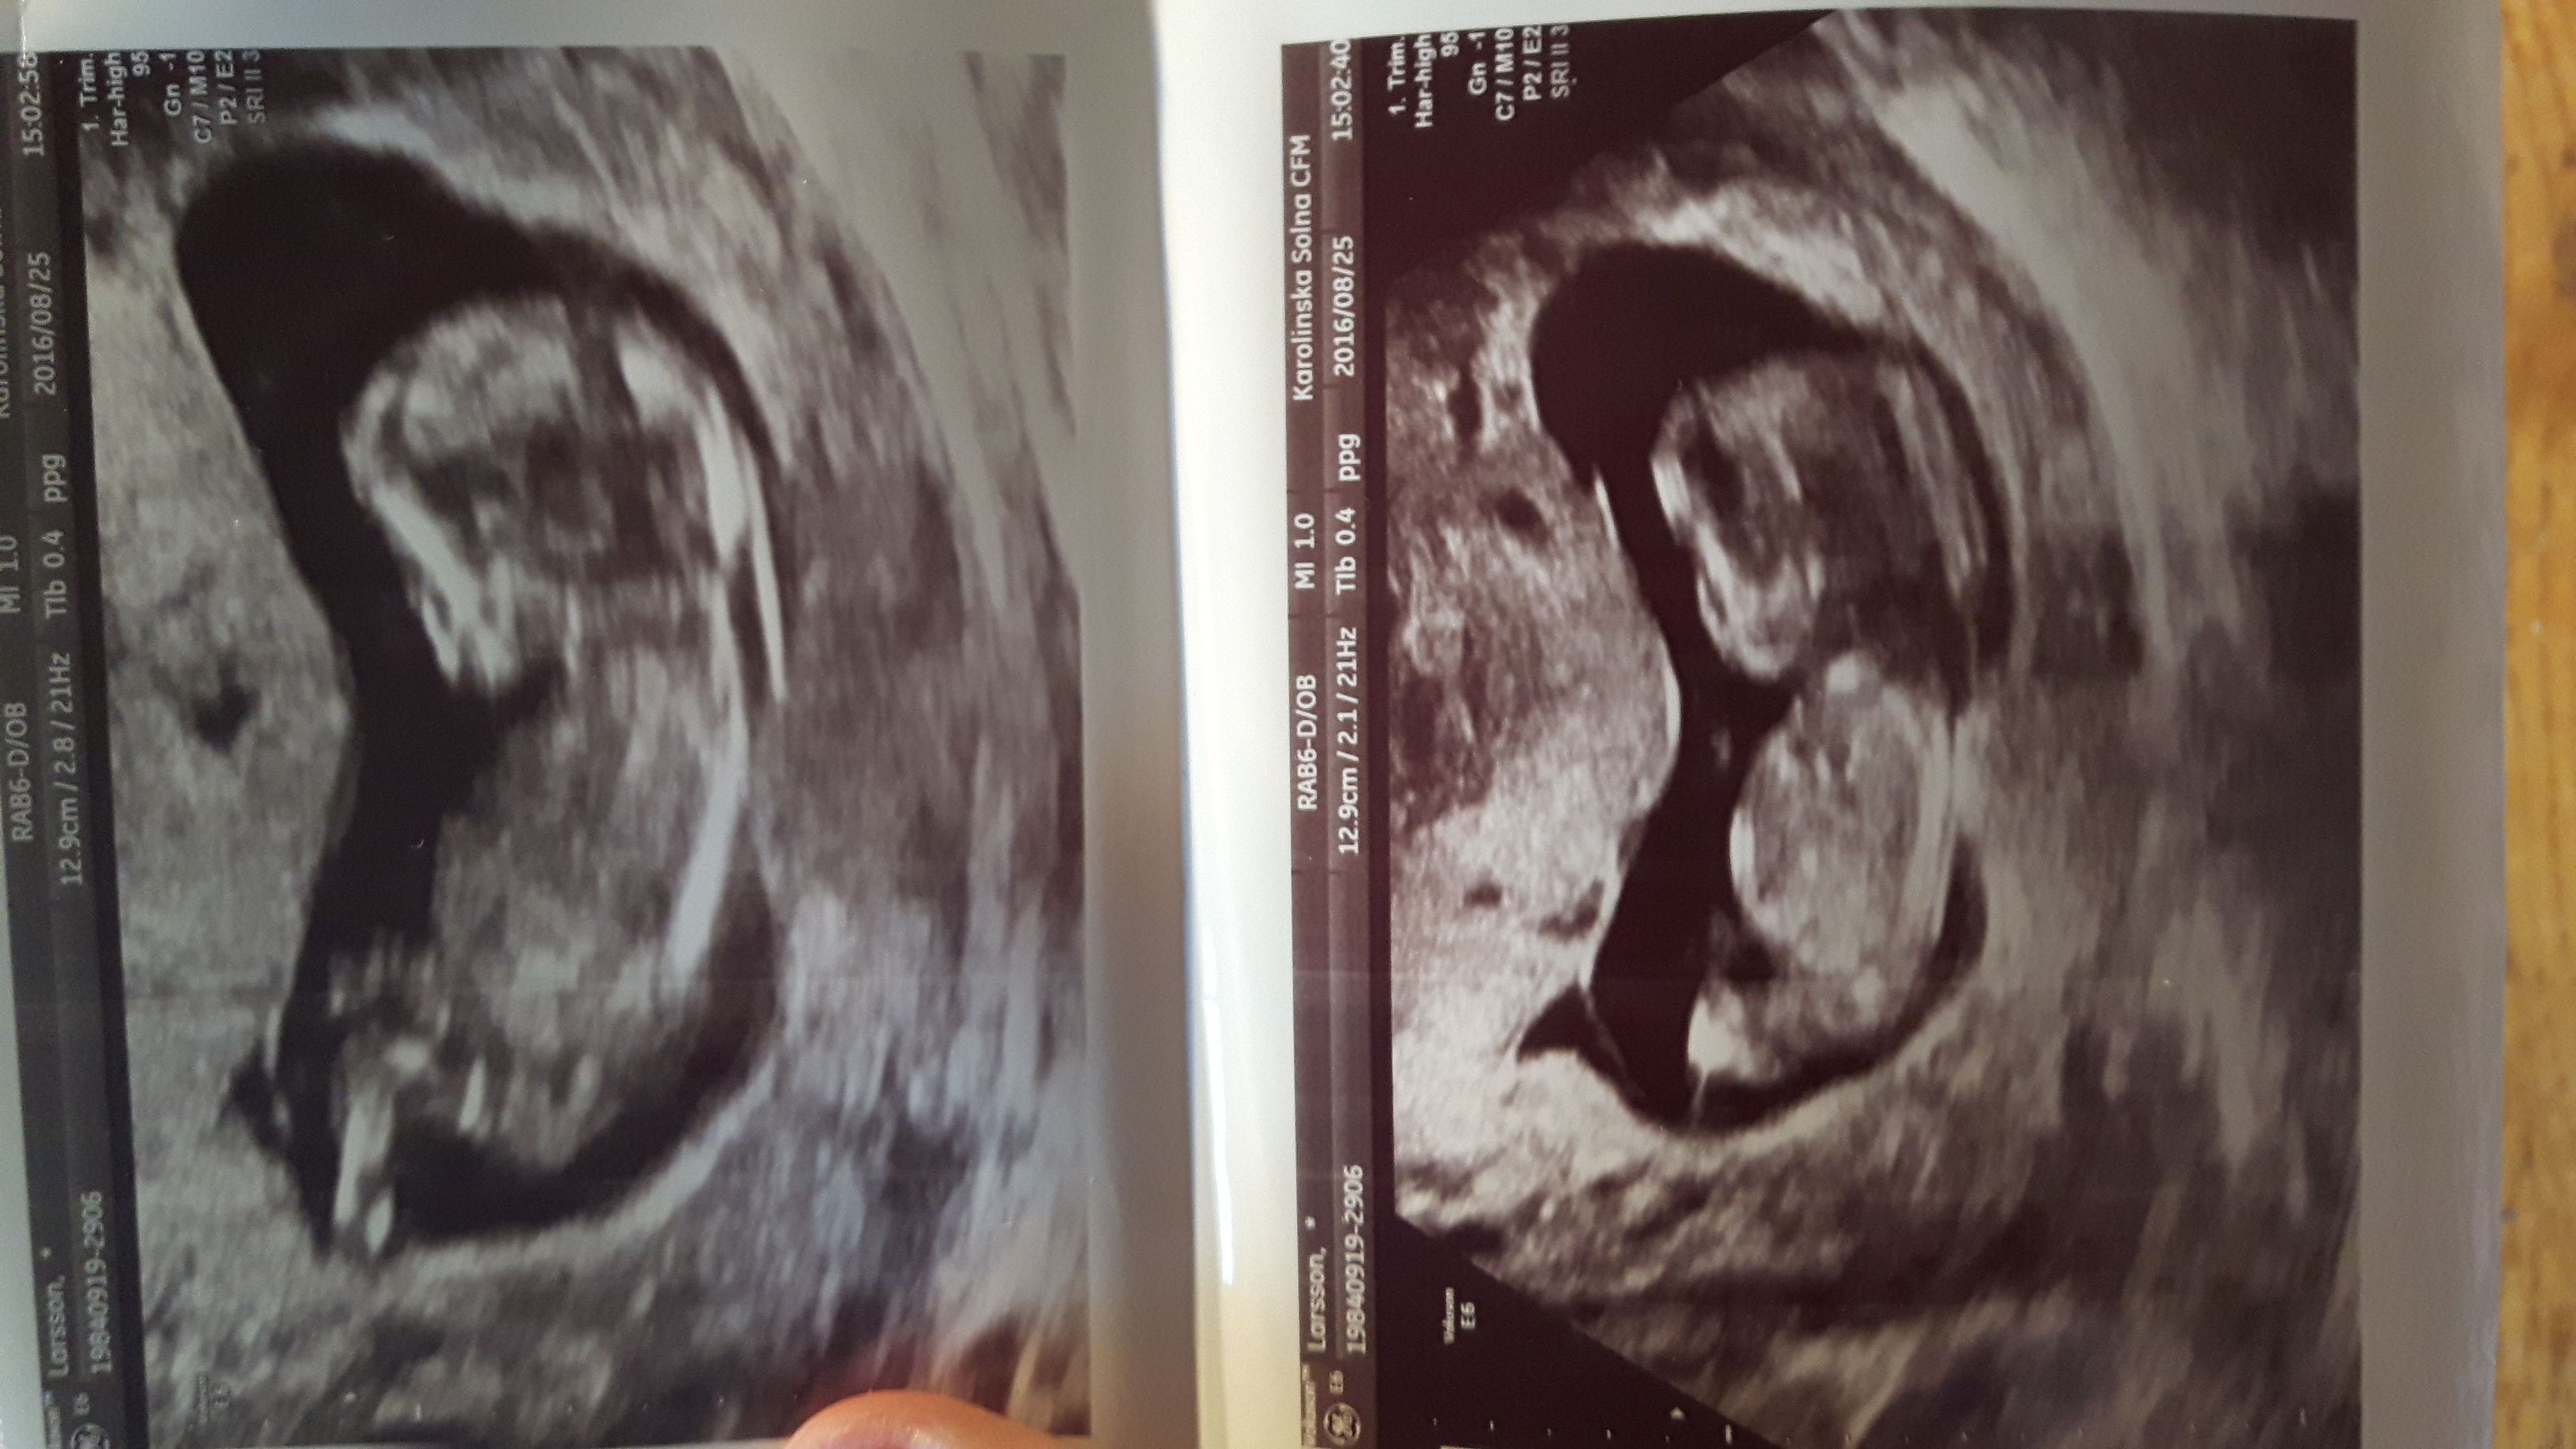

From week 13Attachment 32827

Girl based on second picture x

Girl!

Girl :happy:

Oh bad that I Was Dreaming of a boy. I have two Girls

Don't lose hope, it's flat but not typically long and thin. My youngest boy's was similar looking and had me thinking girl, but like yours it was quite short - he's all boy!x